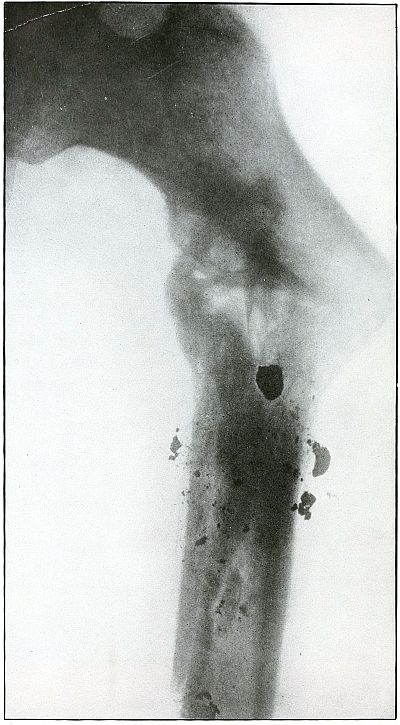

Plate 52.

[Pg 115]

Rifle—Plate 52.

LOWER EXTREMITY.

Gunshot Fracture of the Upper Shaft of the Femur.

The course of the bullet was anteroposterior and pierced the axis

of the shaft of the femur with three radiating lines of fracture,

resulting from the perforating action of the bullet striking the bone

at long range and with greatly reduced energy.

This plate shows the lateral separation of large fragments,

which is typical of gunshot wounds of long range.

Such wounds are usually not infected.

Emergency treatment is antiseptic dressing and coaptation with

extension and temporary splint, so that it may support the bone for

transportation and may be easily removable at place of continued

treatment.

In these cases with lateral separation of fragments, it is imperative

to supplement extension with pressure in a line perpendicular to the

long axis of the femur.

[Pg 116]